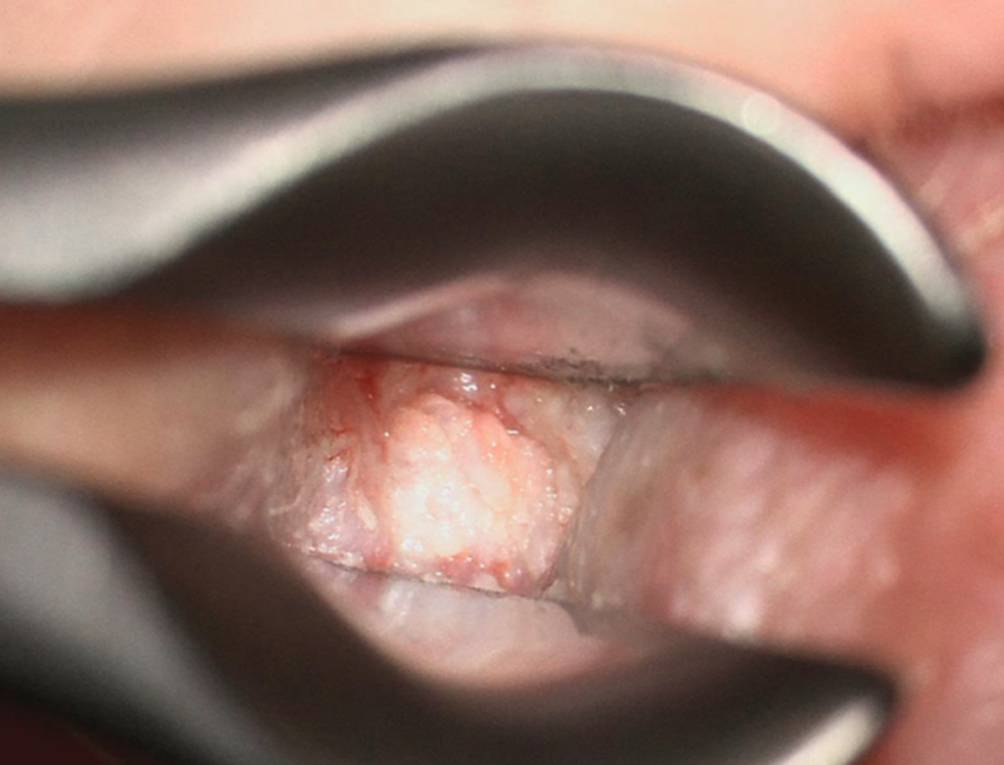

Abb. 1

Typischer ohrmikroskopischer Befund einer Otitis externa necroticans (OEN) mit diffuser Entzündung des Gehörgangs und Granulationsgewebe im hinteren Bereich. Trommelfell vollständig von der Granulation überdeckt, daher nicht beurteilbar

Patient:innen mit OEN präsentieren sich typischerweise mit starken Ohren- und Kopfschmerzen und Otorrhö, welche auf die topische Therapie nicht suffizient ansprechen. Häufig wird über eine nächtliche Schmerzzunahme berichtet, und durch eine entzündliche Beteiligung des Kiefergelenks können verstärkt Schmerzen beim Kauen auftreten. Der typische ohrmikroskopische Befund zeigt zusätzlich zu einer diffusen Entzündung des Gehörgangs auch Granulationsgewebe (Abb. 1; [10]).